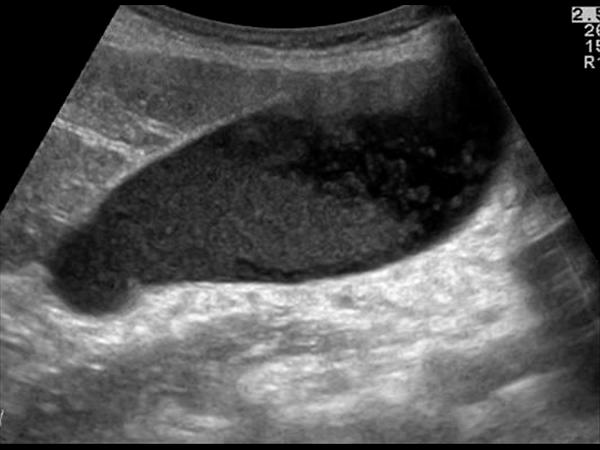

Courvoisier's GB

Distension without wall thickening

due to obstruction distal to the cystic duct

*Panncreatic head mass

* Duodenal papilla mass

*CBD mass